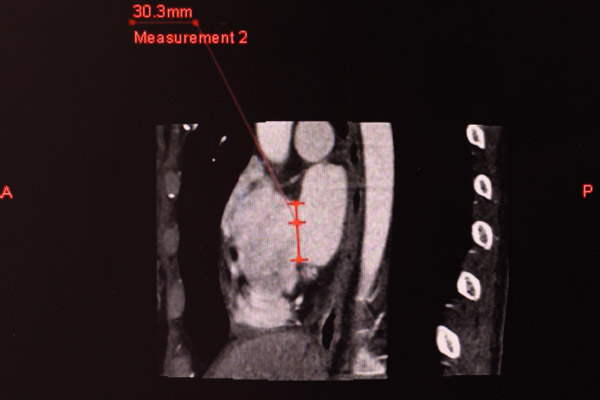

“下腔型房間隔缺損不是介入治療的適應癥,這種先心病過去均需要通過開放手術才能解決。”我院心血管內科副主任醫師陳世忠介紹,但是現在這一情況有所改變,下腔型房缺本身還有幾種亞型,通過我院配備有目前最先進的320排CT,除了能夠重現人體臟器的立體結構外,還能實時反映患者整個器官功能狀態和血流運行的情況,可以清晰地看到房間隔缺損的位置以及大小,明確房室關系及血管走向,遴選出合適封堵的亞型,輔助我們制定最優手術方案。

在與楊某充分溝通后,患者強烈要求進行微創手術治療,希望醫生能夠想想辦法,由于患者心臟缺損邊緣至下腔靜脈的距離不足1mm,對于介入手術來說難度極大,為了解決其面臨的難題,心血管內科召集放射科和超聲科團隊一起討論會診, 通過320排CT生成的動態立體圖像,精確計算,反復對比研究,再三斟酌決定大膽嘗試,用了足足兩天時間做好了手術方案和術前準備。